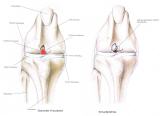

Der Kreuzbandriß beim Hund ist im Gegensatz zum Menschen in 90 % der Fälle nicht durch einen Unfall verursacht sondern eine Folge von degenerativen Prozessen im Gelenk wie z. B. einer Gelenksarthrose. Begünstigt wird diese Erkrankung z. B. durch Übergewicht. Deshalb geht der betroffene Hund meistens ohne deutlich erkennbare Ursache plötzlich lahm. Beim Neufundländer und Boxer ist eine genetische Anlage bewiesen. Generell gilt aber, dass vor allem ältere kastrierte Hündinnen (> 6-7 J) mit Übergewicht betroffen sind. Die betroffenen Tiere zeigen eine zumeist deutliche Lahmheit am betroffenen Hinterbein. Die Diagnose wird beim Tierarzt durch eine Ganganalyse, den Sitztest, eine umfassende klinische Untersuchung (z. B. Schubladenphänomen, Tibiakompressionstest) und Röntgendiagnostik gestellt. Eine Röntgenuntersuchung in mind. 2 Ebenen ist zwingend erforderlich um weitere Erkrankungen (z.B. eine Arthrose oder eine OCD) festzustellen.